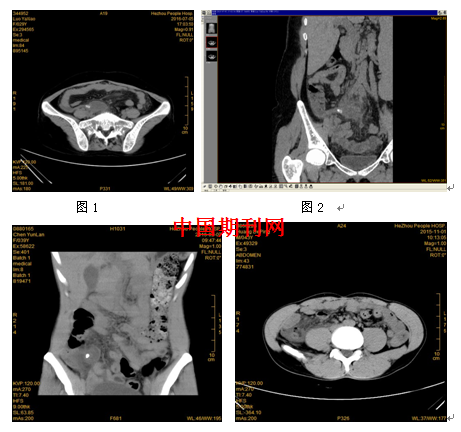

多层螺旋CT在穿孔阑尾炎中的诊断价值分析

[摘要] 目的分析急性阑尾炎的多层螺旋CT(MSCT)征象,提高CT对急性阑尾炎诊断的准确性。方法对126例手术病理证实为急性阑尾炎的腹部多层螺旋C